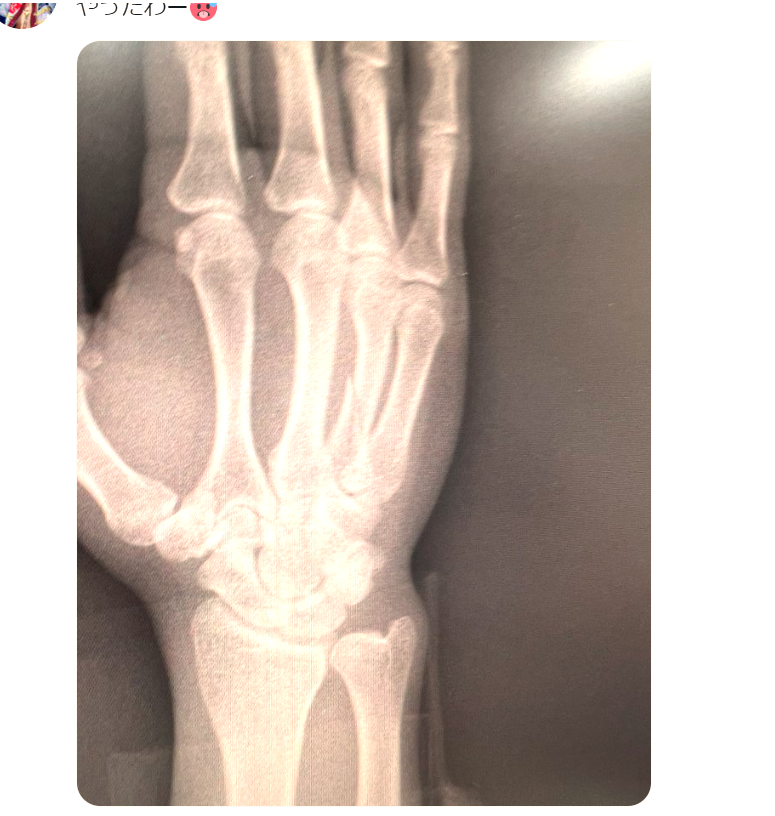

YUSHIが公開した右手のレントゲン写真@yushi0409sakura